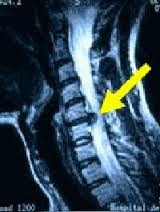

19 de febrero de 2014

Una nueva investigación llega a la conclusión de que la acupuntura es eficaz para el tratamiento de lesiones en el cuello. Los investigadores tienen pruebas de laboratorio que la acupuntura restaura la curvatura en la columna vertebral que se perdió debido a un impacto. Investigadores encuentran la acupuntura como eficaz en la restauración de rango de movimiento cervical en casos de daños en los discos intervertebrales. Además, los resultados de los rayos X confirman que la acupuntura beneficia a la columna cervical. La acupuntura restaura significativamente curvatura normal en el cuello después de la lesión.

En un experimento de laboratorio modelo de conejo controlada, acupuntura restaura rango de movimiento cervical que se ha incidido en la espondilosis, una afección dolorosa de la columna vertebral debido a la degeneración del disco. No se encontraron problemas de curvatura de la columna vertebral Espondilosis relacionadas a responder con resultados positivos con la acupuntura. El estudio demostró que la acupuntura restaura eficazmente curvatura cervical normal en casos de espondilosis. Además, algunos casos demostraron éxito ensanchamiento del agujero intervertebral como resultado de tratamientos de acupuntura.

Esta investigación la acupuntura educación continua ha surgido mientras que otro estudio reciente halla que la acupuntura es más eficaz que el fármaco Meloxicam para el tratamiento de las hernias de disco cuello. En una investigación de 420 pacientes, la acupuntura ha demostrado resultados clínicos superiores sobre el AINE (antiinflamatorio no esteroideo). La acupuntura fue significativamente más eficaz en la reducción a largo plazo ya corto plazo de los síntomas patológicos y síntomas causados por hernias de disco cuello. La acupuntura fue más exitoso en la restauración de la movilización cervical incluyendo la flexión lateral, de vuelta de flexión y giro lateral. La acupuntura también fue significativamente más eficaz en la reducción del dolor, entumecimiento y dolor. Objetivo prueba confirmó que la acupuntura ejerce beneficios clínicos superiores sobre el Meloxicam. Los reflejos tendinosos, pruebas de tracción del plexo braquial y pruebas de gatera mostraron mayores mejorías a corto y largo plazo con la acupuntura.